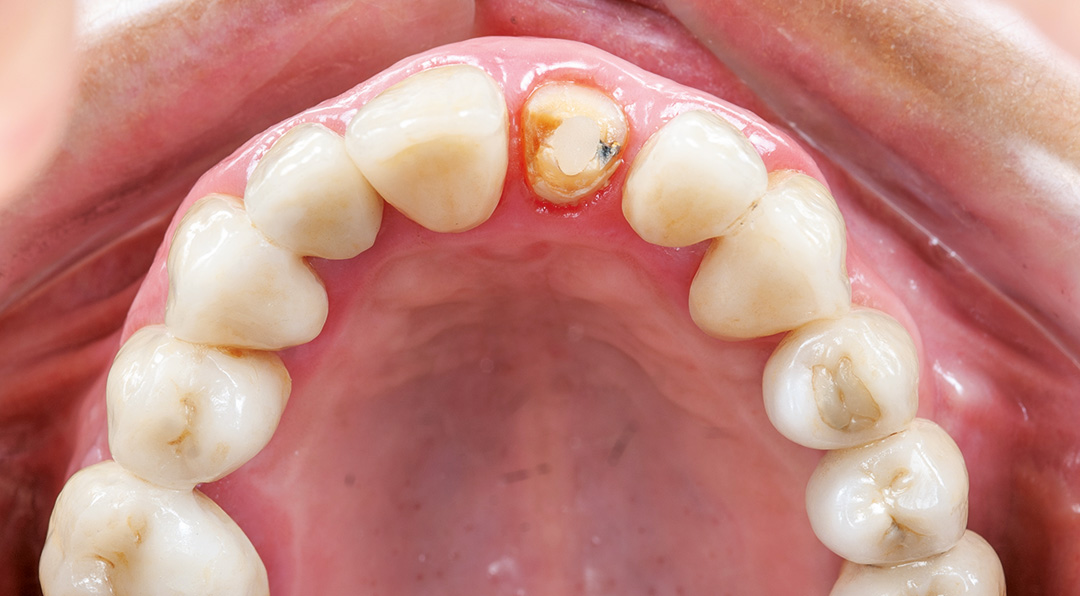

A patient presented with a horizontal fracture of the upper left lateral incisor (tooth 1.2), with no clinical signs of suppuration or bleeding. The periodontal phenotype was thin, and the buccal bone wall was minimally thick, increasing the risk of soft tissue recession following extraction. A minimally invasive and digitally planned treatment was chosen to preserve tissue architecture and ensure a predictable aesthetic result.

A 67-year-old female patient presented with a broken central incisor. The tooth in question had been restored with a crown several years ago, but this had since detached. The patient did not report being in pain, though she was concerned about the appearance of her smile. Her initial assessment revealed no relevant medical history and she was a non-smoker.